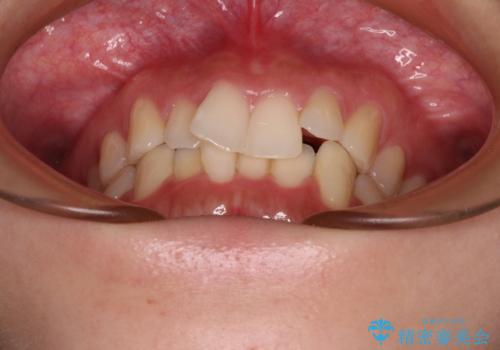

- 前歯のデコボコを気にして来院された患者様です。

全体的にデコボコが多く、特に下の前歯は隠れてしまうほどの状態でした。

左右ともに奥歯の咬み合わせが理想的な位置にあったこともあり、患者様のご希望通り、インビザラインにて矯正治療を行うこととしました。